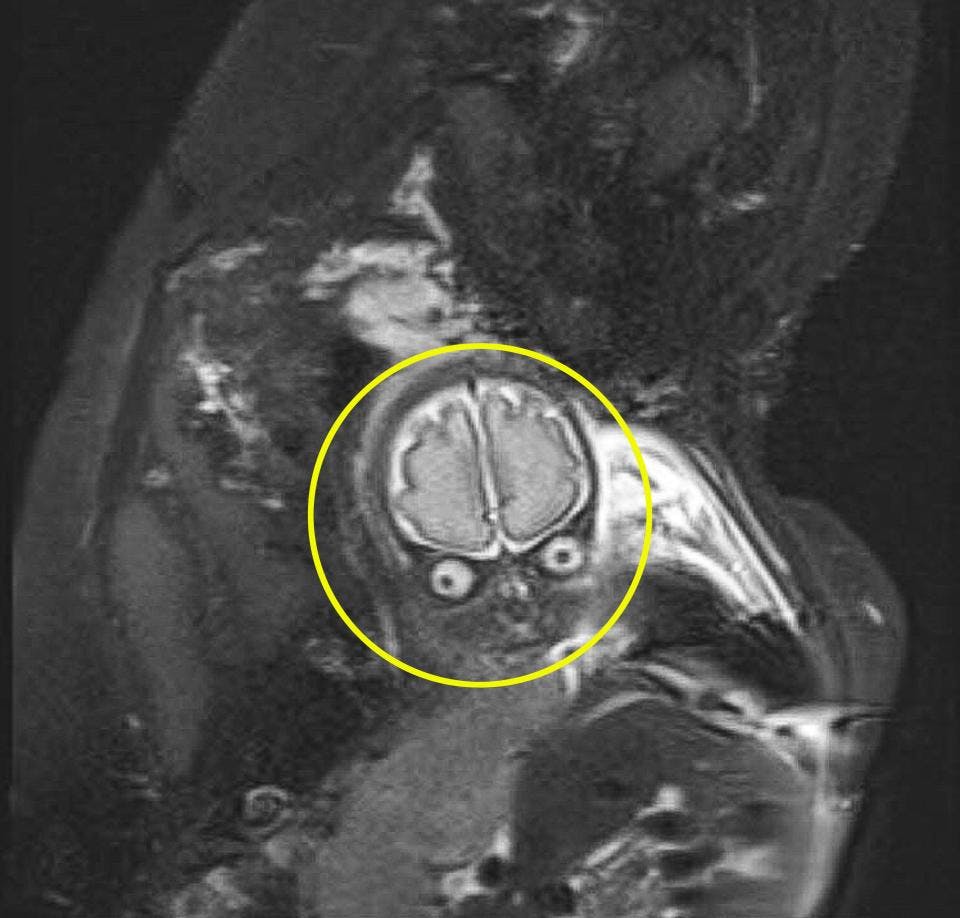

IRM Sud Ouest has been providing Montreal with MRI & Ultrasound scanning services for over 10 years Our experienced staff will make your visit as stressfree as possible!• IRM L'IRM permet d'apprécier des critères pronostics supplémentaires (10)(11) • Aspect du cartilage surfacique (œdème chondral, fissures) • Interface os épiphysaire/fragment (tissu de granulation sous la forme d'un liseré en hypersignal T2, / associé à des microkystes)

L'IRM étudie principalement les tissus mous et les structures liquidiennes, notamment les différentes structures dans les cavités auriculaires ainsi que le nerf auditif L'IRM peut montrer une infection de l'oreille interne (labyrinthite), une tumeur ( neurinome, cholestéatome ) ou une malformation Carta De Um Bebê Para o Irmão Mais Velho Eu sei que a minha chegada na nossa família está sendo muito difícil para você Antes de eu chegar, você era o centro das atenções O papai e a mamãe só tinham olhos para você e tudo era feito pensando em você, somente você Agora que eu estou aqui, eles passam horas comigo, tentando meCertains sont des protocoles qui doivent être suivis par le laboratoire, d'autres